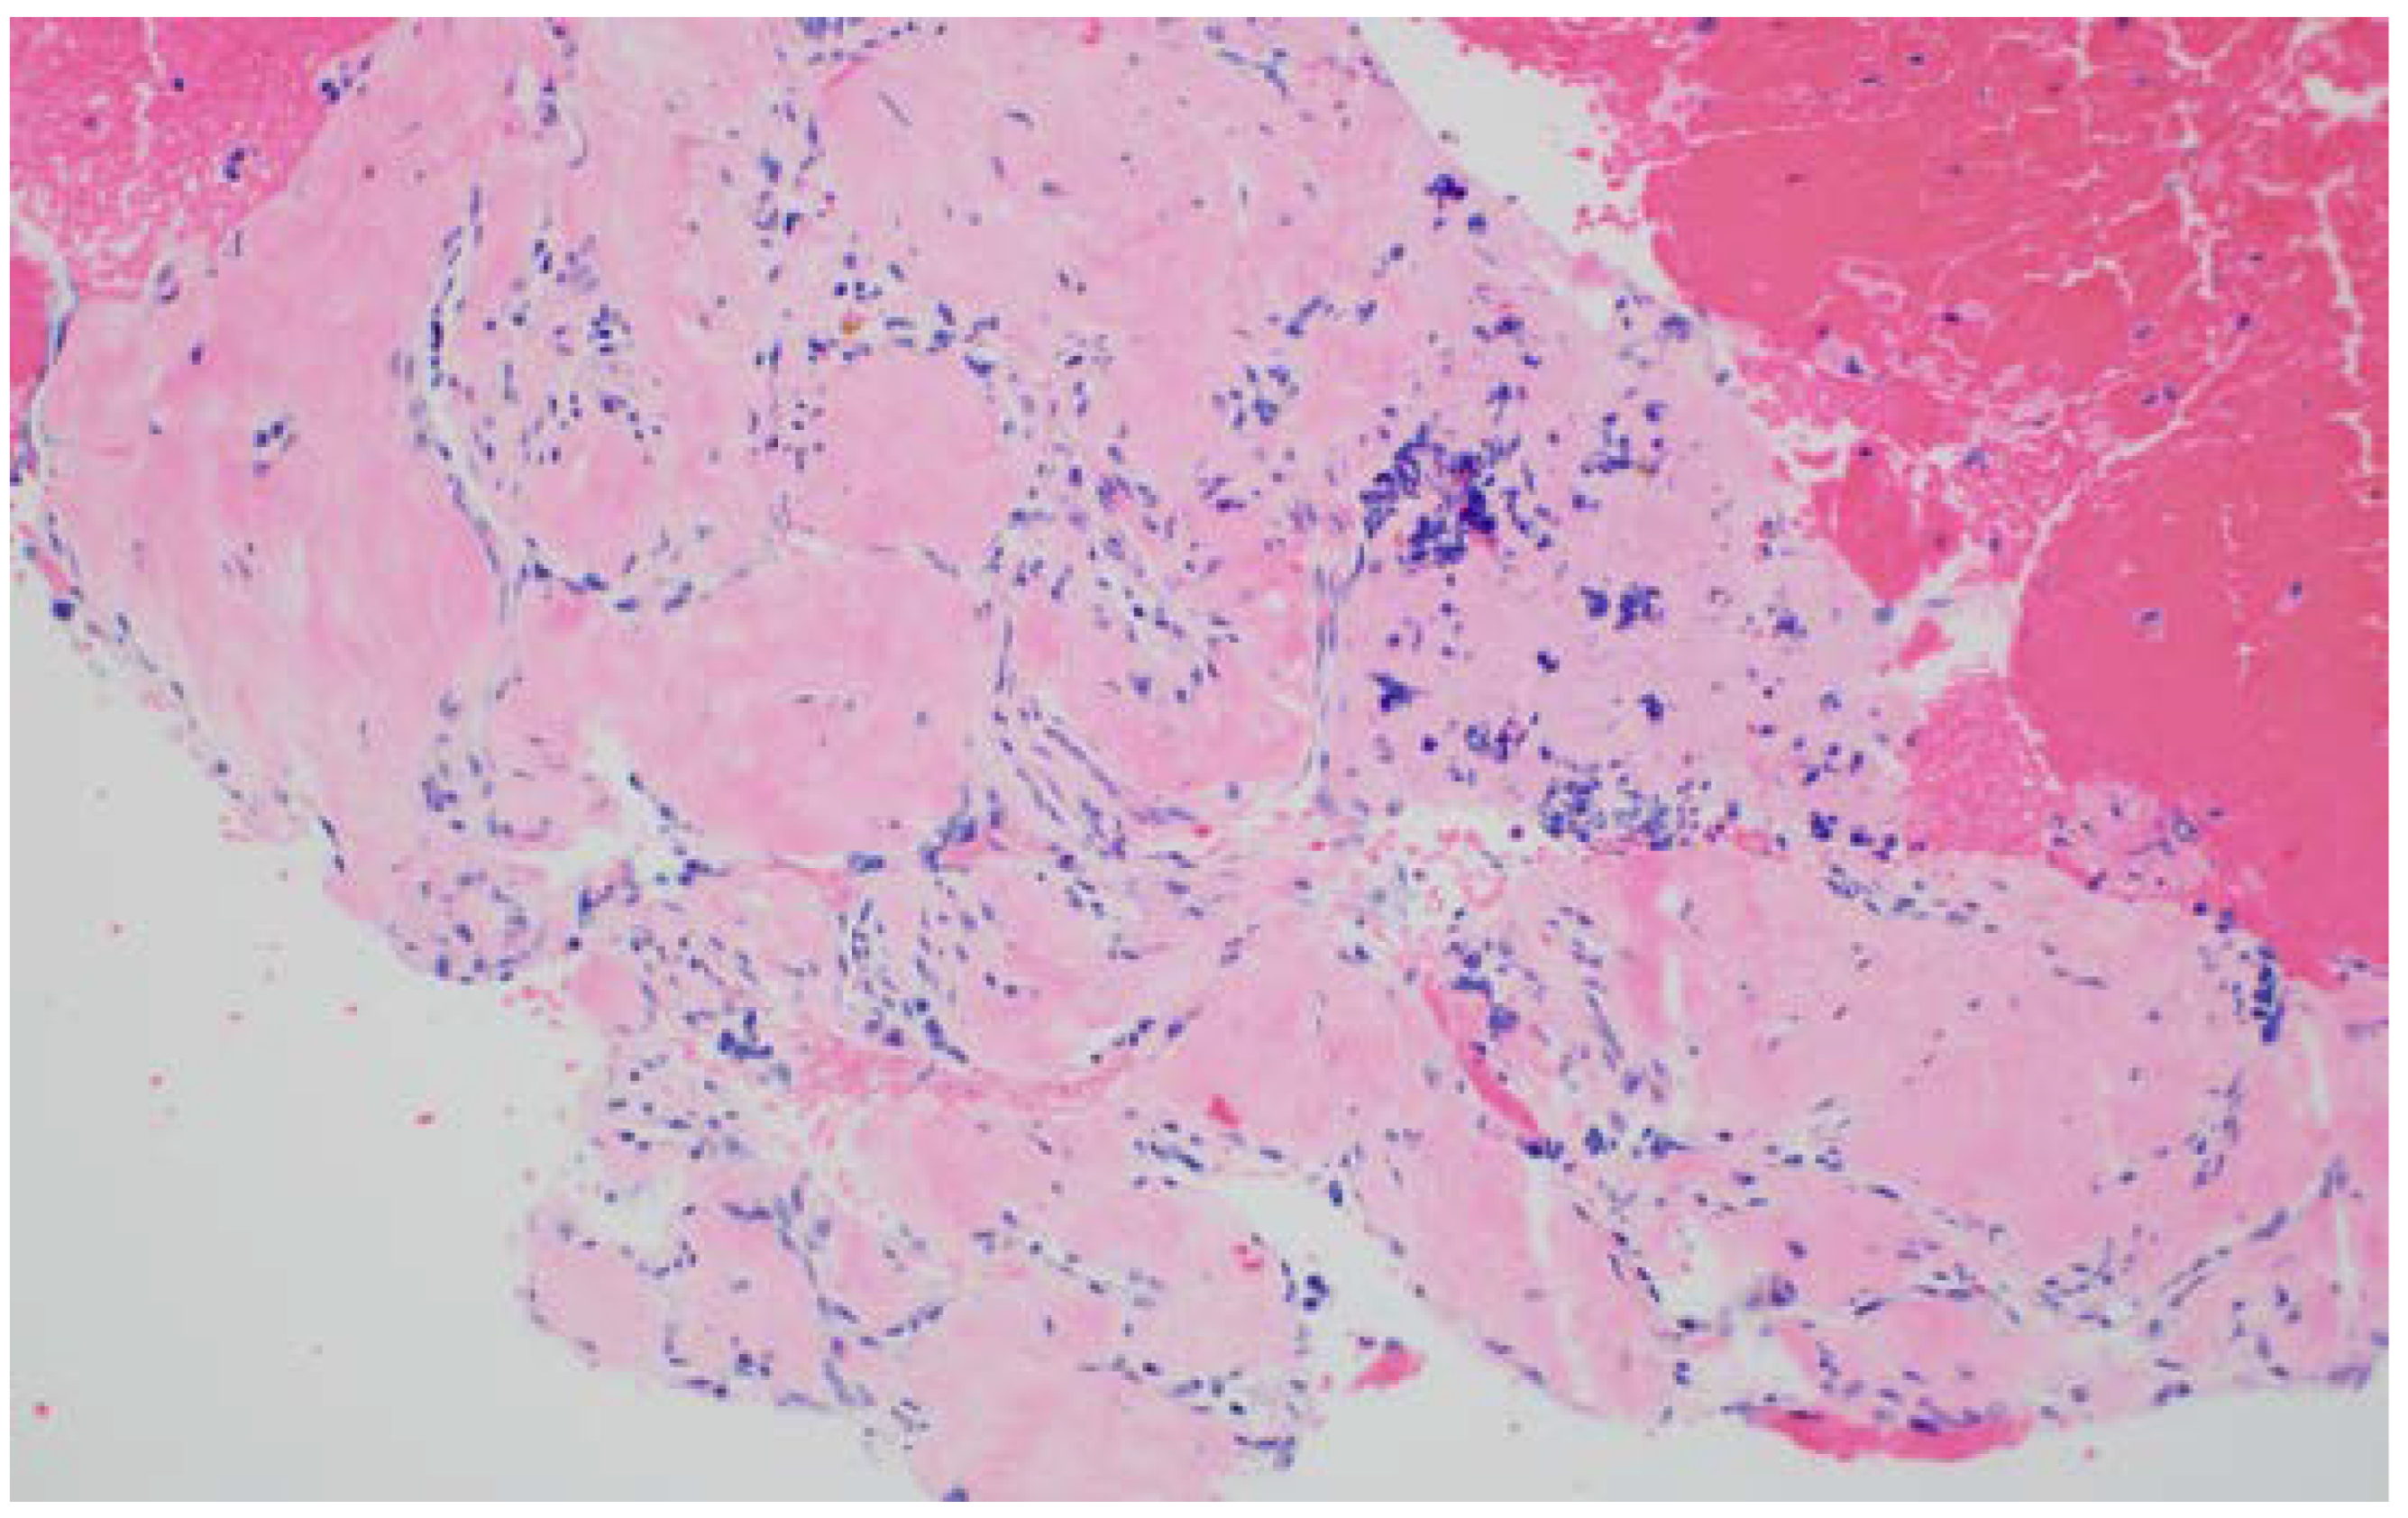

4. EUS-Fluid Acquisition

5. EUS-Tissue Acquisition

5.2. Other EUS-TA Modalities